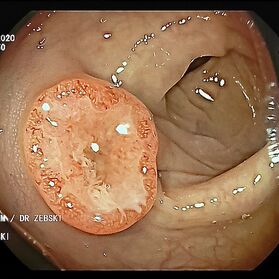

Die Darmspiegelung hilft, dass Darmkrebs gar nicht erst entstehen kann. Denn während der Untersuchung werden auch Polypen entfernt, aus denen sich der Darmkrebs in der Regel entwickelt. Von allen Maßnahmen zur Früherkennung dieser Polypen besitzt die Koloskopie die höchste Empfindlichkeit. Sie weist kleinste Polypen, aber auch Darmkrebs nach, der noch keinerlei Symptome macht. Die Abtragung dieser Polypen erfolgt direkt, wenn sie entdeckt werden. Das geschieht völlig schmerzfrei. Durch die Abtragung der Polypen kann die Entstehung von Darmkrebs effektiv verhindert und die krebsbedingte Sterblichkeit gesenkt werden.